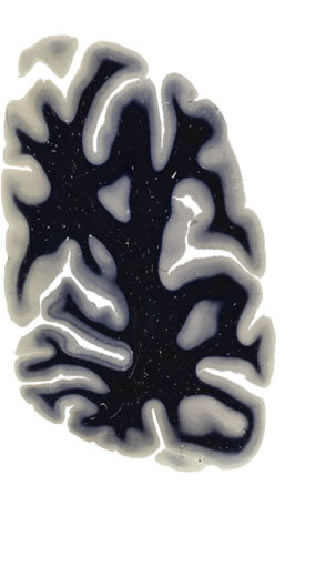

Hi-Resolution Sections · Cells (Nissl Staining) · Virtual Microscopy

Frontal sections (Nissl) from the Atlas Brain:

Macroscopy

Slice ID:

r4-1024

Plate NR:

60

Position:

64,5 mm